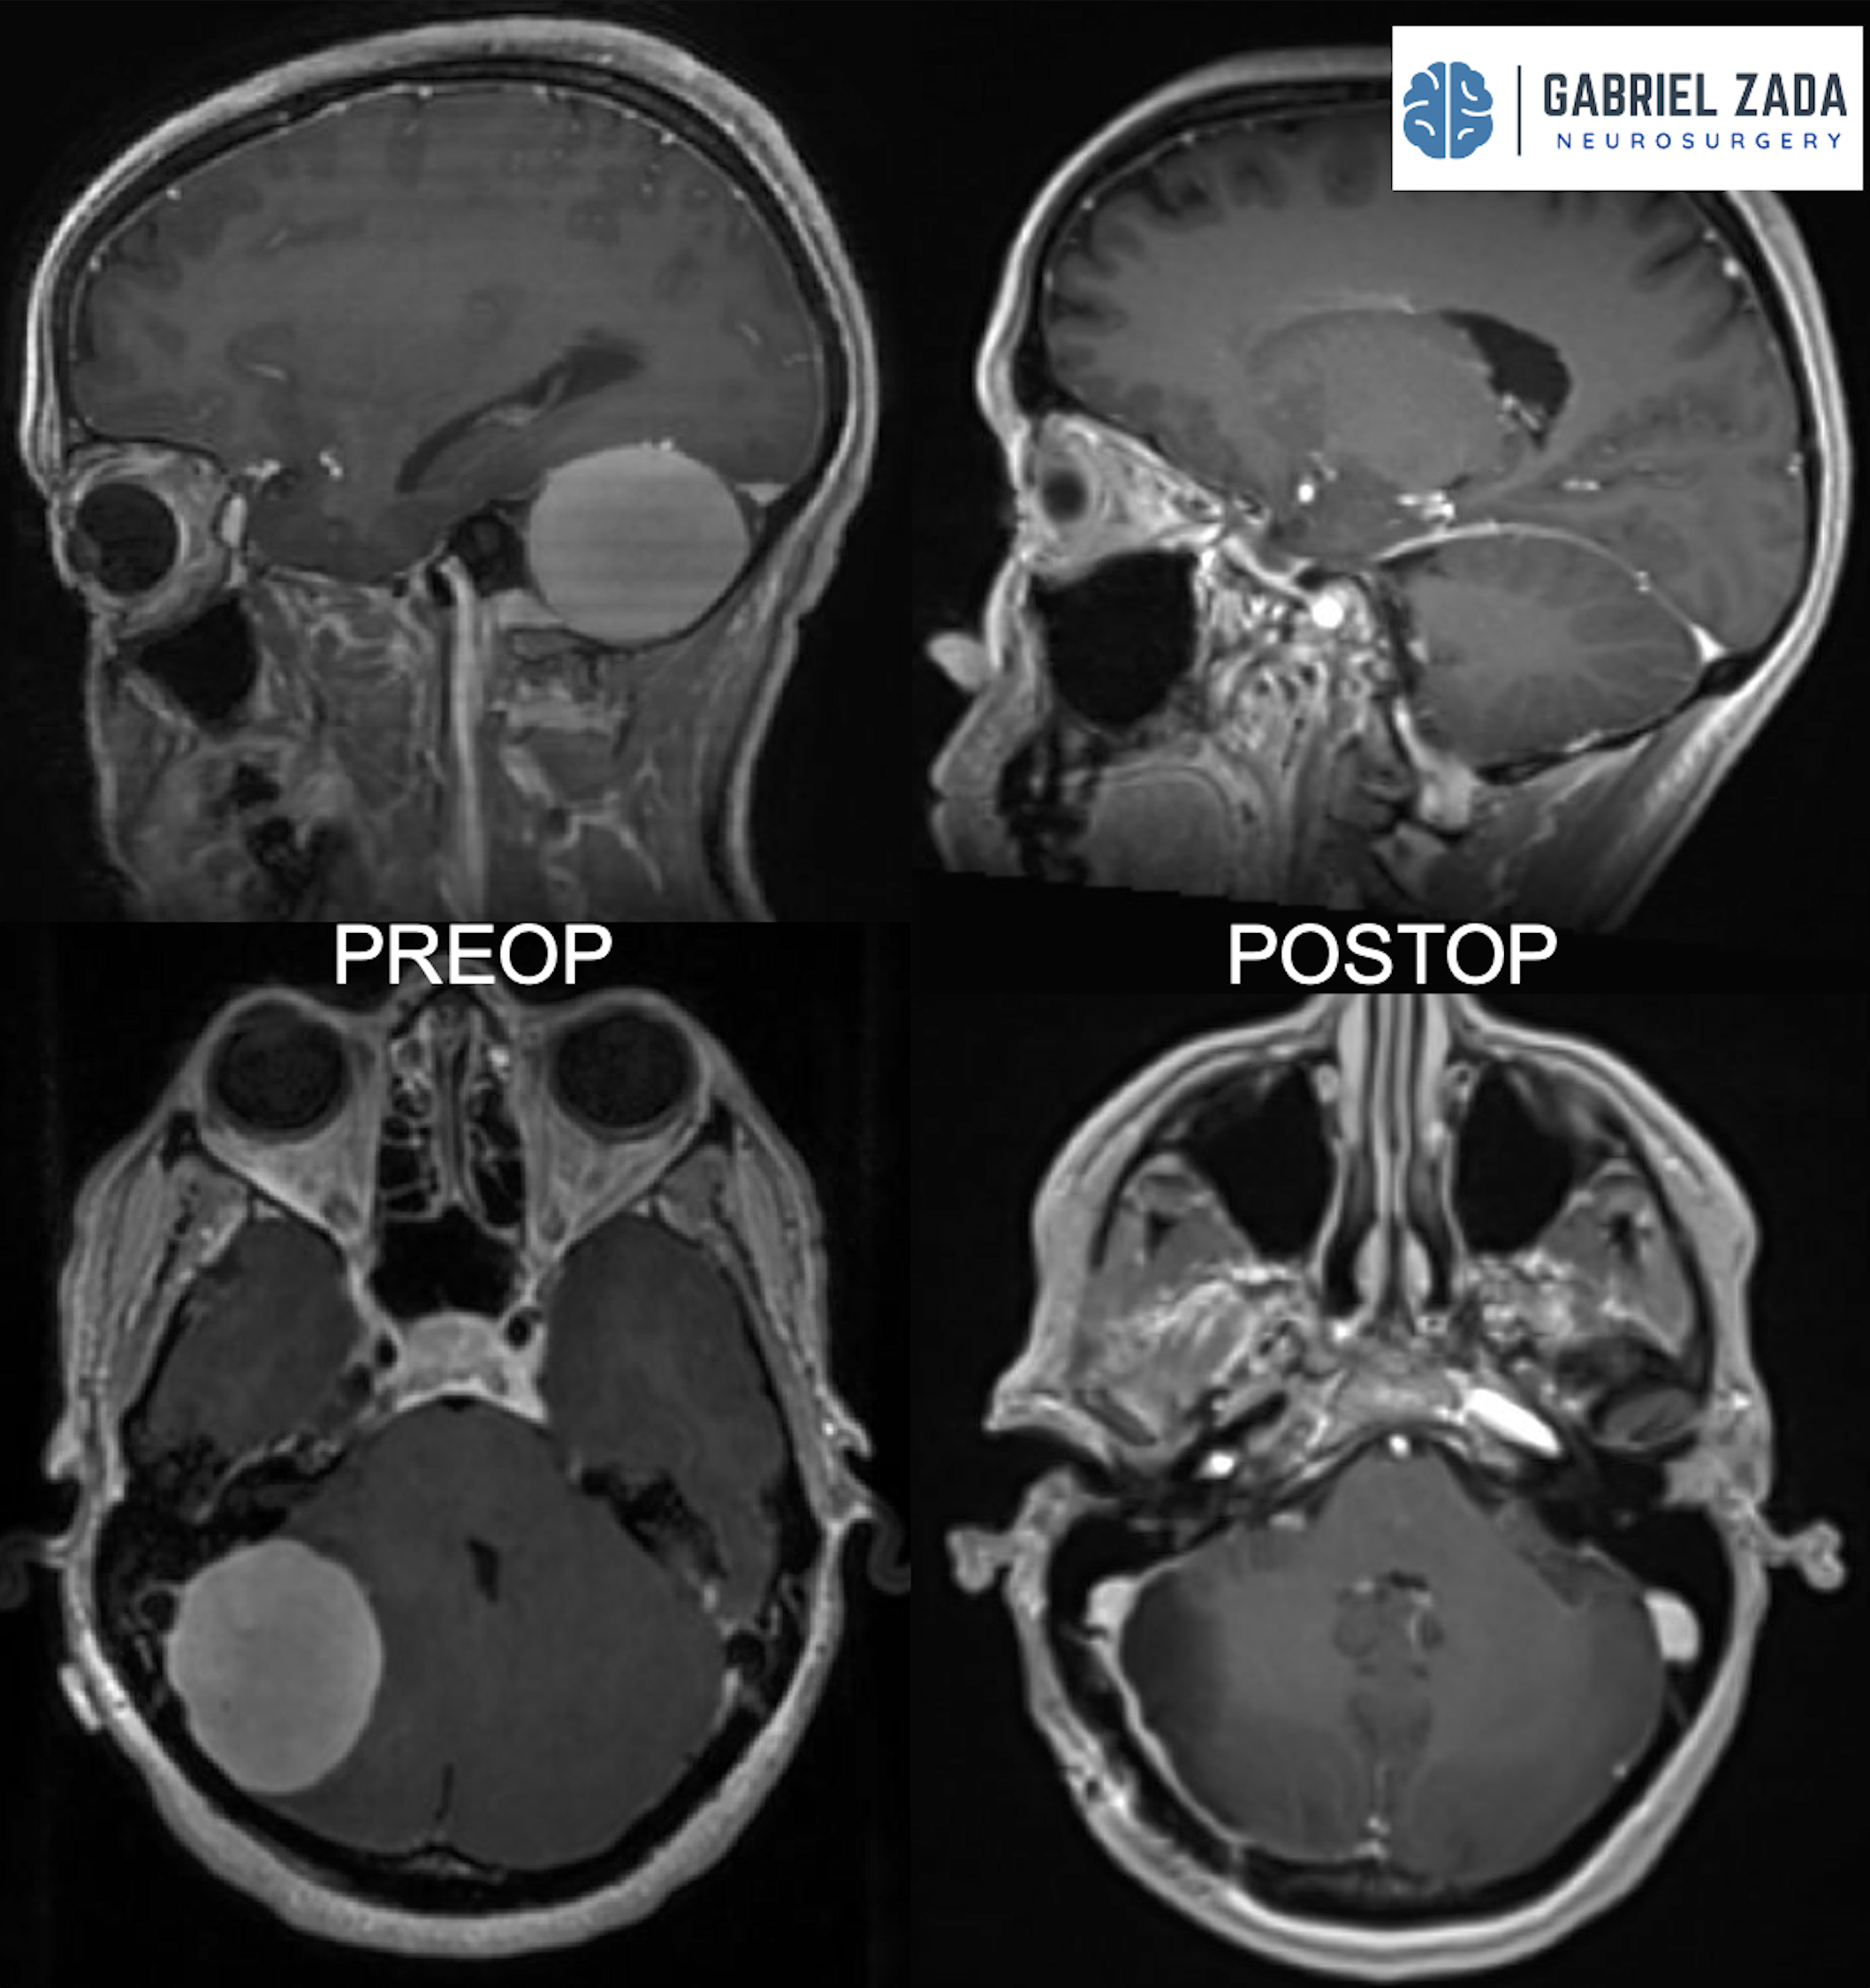

Explore this comprehensive gallery featuring pre‑ and post‑operative imaging of patients with skull‑base tumors treated by Gabriel Zada, MD, MS, FAANS, FACS. These cases highlight Dr. Zada’s expertise in advanced neurosurgical techniques and outcomes.

*Representative cases shown for educational purposes. All images de-identified. Individual results vary.